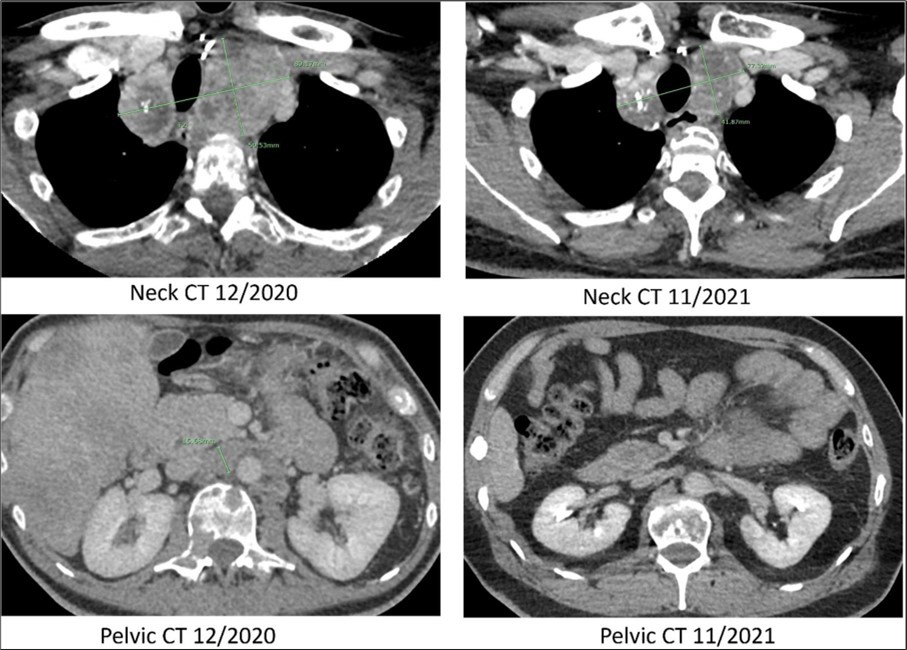

Figure 2.Computed tomography. CT scans of the neck and pelvis with contrast in December of 2020 (prior to Pralsetinib) and in November of 2021 (eleven months after the start of Pralsetinib). The 2020 neck CT showed a large mass at the thoracic inlet measuring 89mm x 50mm. In 2021 this same mass post treatment had decreased in size to 77mm x 41mm. The 2020 pelvic CT showed a retroperitoneal lymph node enlargement to 15mm, which resolved on the 2021 scan.

The patient was re-referred to the Mays Cancer Center/UTHSA in November of 2020. The patient reported significant mobility issues and severe pain, rating a 3 on the Eastern Cooperative Oncology Group Performance Status (ECOG PS). Circulating tumor DNA (ctDNA) analysis (Guardant360) identified a RET 898-901Del and reported as a variant of unknown significance. Since the deletion was in the activation loop of RET kinase, the treating physician considered that the mutation was constitutively activating RET kinase. The patient was treated with Pralsetinib a small molecule inhibitor targeting the ATP-binding site of the RET kinase in December 2020 with a starting dose of 100mg per day with dose escalation every week to 400mg by mouth (PO) daily (QD). In January 2021 the patient noticed an improvement in quality of life (ECOG PS improved 2) with a significant decrease in serum calcitonin and CEA levels and decreased tumor size. The 400 mg PO QD dosing lead a decrease in platelet count to 51 K/mL in mid-February 2021. Pralsetinib was withheld for five weeks to allow for platelet recovery. In the interim the serum calcitonin level increased with disease progression. The patient was restarted at 200mg of Pralsetinib PO QD in March 2021 which was better tolerated with no further symptoms or signs of toxicity. The Pralsetinib treatment improved the patient’s mobility, pain, and over all quality of life, rating a 0 on the ECOG PS by September 2021.